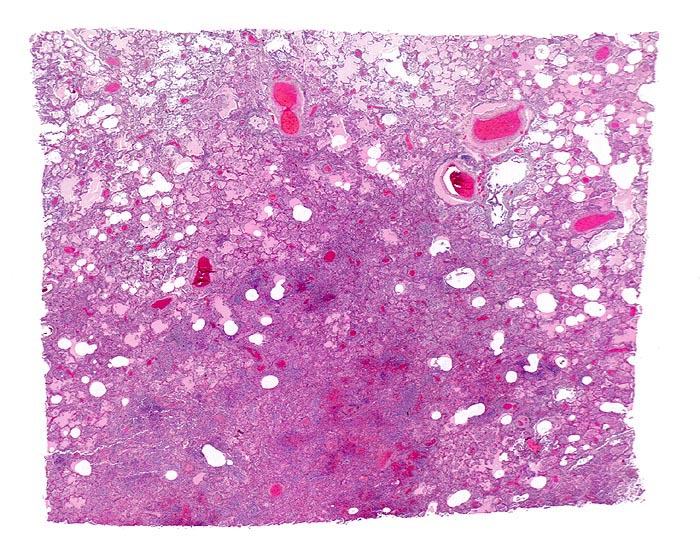

Bronchopneumonie

Lunge

Die Alveolen sind gefüllt mit rosafarbener Ödemflüssigkeit. Der unscharf begrenzte bläuliche Herd entspricht einem pneumonischen Infiltrat (Herdpneumonie) mit intraalveolärer Ansammlung neutrophiler Granulozyten.

Nach dem Verteilungsmuster der entzündlichen Infiltrate werden alveoläre und interstitielle Pneumonien unterschieden. Die alveolären Pneumonien werden unterteilt in die Lobärpneumonie und die Herdpneumonie. Ätiologische Pneumonie-Klassifikationen sind nur bedingt auf pathologisch-anatomische Befunde zu übertragen, da nur wenige Erreger charakteristische morphologische Veränderungen bewirken. Eine Lobärpneumonie tritt auf, wenn die Erreger die Alveolarräume so ausgedehnt und rasch befallen, daß sie erst vor anatomischen Grenzen (z.B. einem Lappenspalt) Halt machen.